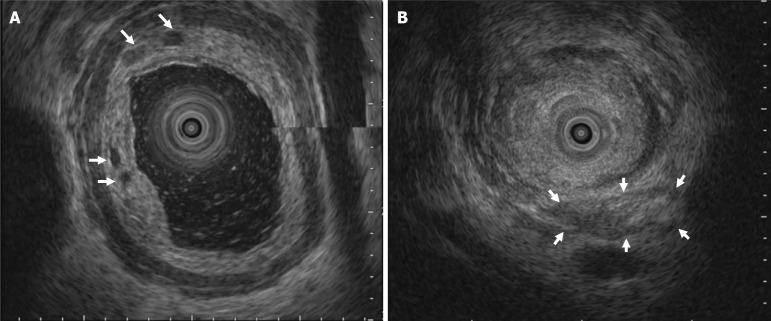

We report the case of a 60-year-old man who presented with progressive dysphagia, weight loss, and nocturnal cough. Esophagogastroduodenoscopy, timed barium esophagogram, and high-resolution manometry were conducted. The results of these investigations supported a diagnosis of type II idiopathic achalasia. However, preoperative computed tomography revealed atypical findings, which prompted further evaluation. Repeat endoscopy with magnifying narrow-band imaging identified abnormal mucosal and vascular patterns, and endoscopic ultrasound demonstrated hypoechoic submucosal lesions with involvement of the muscularis propria. Targeted biopsies confirmed moderately differentiated ESCC. Positron emission tomography revealed extensive metastatic disease; therefore, the patient was diagnosed with stage IVB ESCC. Peroral endoscopic myotomy was aborted, and the patient was referred for palliative chemoradiotherapy.

我们报告了一名60岁男性的病例,该患者表现为进行性吞咽困难、体重减轻和夜间咳嗽。进行了食管胃十二指肠镜检查、定时食管钡餐造影和高分辨率测压法。这些检查结果支持II型特发性贲门失弛缓症的诊断。然而,术前计算机断层扫描显示出非典型表现,这促使进一步评估。重复内镜检查并使用放大窄带成像识别出异常的黏膜和血管模式,内镜超声显示低回声黏膜下病变累及固有肌层。靶向活检确诊为中分化ESCC。正电子发射断层扫描显示广泛转移;因此,该患者被诊断为IVB期ESCC。经口内镜下肌切开术中止,患者被转诊接受姑息性放化疗。